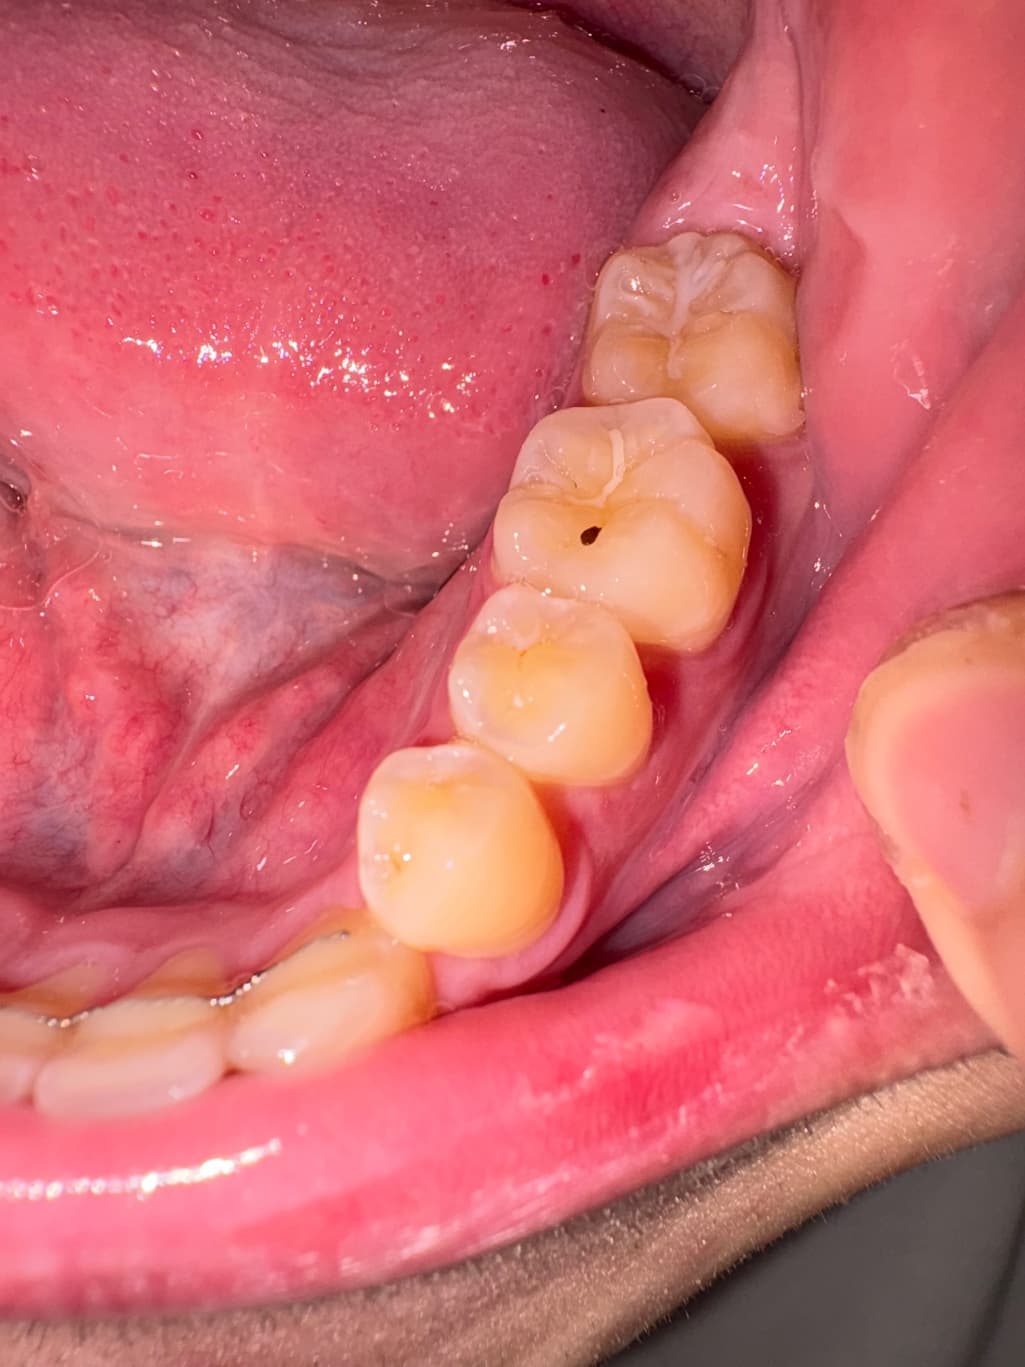

어금니 검은점 이 생겼는데 이거 충치일까요

포도먹다가 이물감이라 해야할지 뭔가 이상해서 봤더니 검은점이 생겼는데

저거 충치일까요 아니면 그냥 이물질인가요

통증은 전혀없습니다

• 1번 째 사진

위 사진만으로는 명확히 알 수는 없으나 색상으로 봤을 때엔 충치보단 이물질인 것 같습니다.

사진상으로는 예전에 치료햇던곳이 파이면서 음식물이 낀게 아닐까 생각됩니다. 일단 제거를 해보시고 제거가 안되면 치과에 가셔서 검진을 받아보시는게 좋을것같습니다.

충치일수도 있지만 단순한 착색 일수도 있습니다 충치라면 치료를 해주는것이 좋으며 착색이라면 간단하게 치과에서 제거할수 있습니다.

자세한 확인을 위해서 치과에서 진료를 받아보는 것을 권유드립니다.

사진상 봤을때 충치의 양상으로 보이진 않고요 음식물이 낀것 같습니다 잘 빼주시기 바랍니다